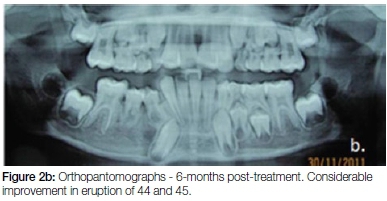

The patient was recalled daily for seven days postopera-tively for irrigation of the socket with betadine and saline. The parents of the patient were taught how to irrigate the socket with these solutions and how to ensure the maintenance of good oral hygiene. Thereafter the patient was recalled fortnightly and periodic trimming of the acrylic extension was done to facilitate eruption of 44 and 45. After three months (Figure 5, a-c), anterior crossbite correction was observed along-with progressive eruption of 44 and 45. The 43 appeared to be improving in its path of eruption. The patient was then advised to discontinue the obturator. Follow-up after one year showed complete eruption of 44 and 45, and no relapse of the crossbites or recurrence of the dentigerous cyst (Figure 2c and Figure 6, a-c).